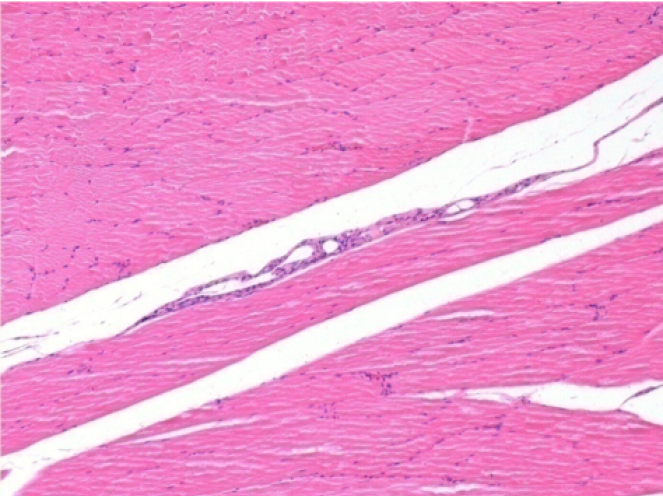

سبعة أشهر بعد حقن إندوبيل

7 أشهر (D210) بعد حقن Endopeel IM 0.1 مل في العضلة أمام الظنبوب اليمنى.

Complete Restitutio ad integrum after 7 months

L : Control-100xD210

R:100xD210

L :Control 50xD210

R50X-D210